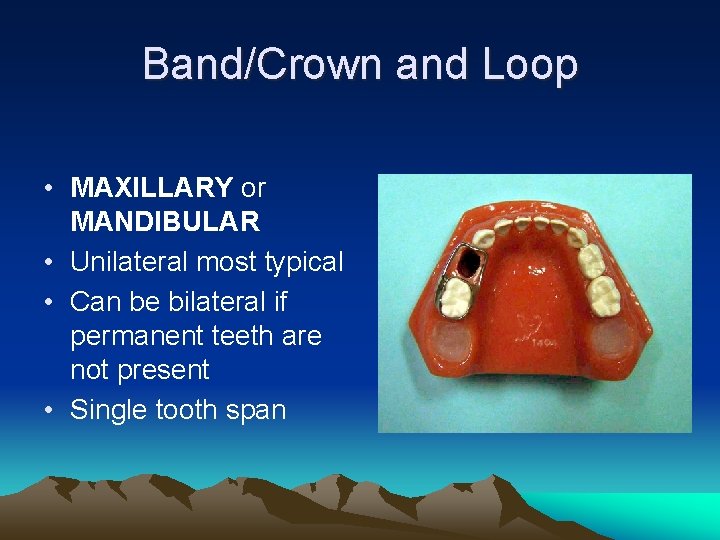

Band/Crown and Loop • MAXILLARY or MANDIBULAR • Unilateral most typical • Can be bilateral if permanent teeth are not present • Single tooth span